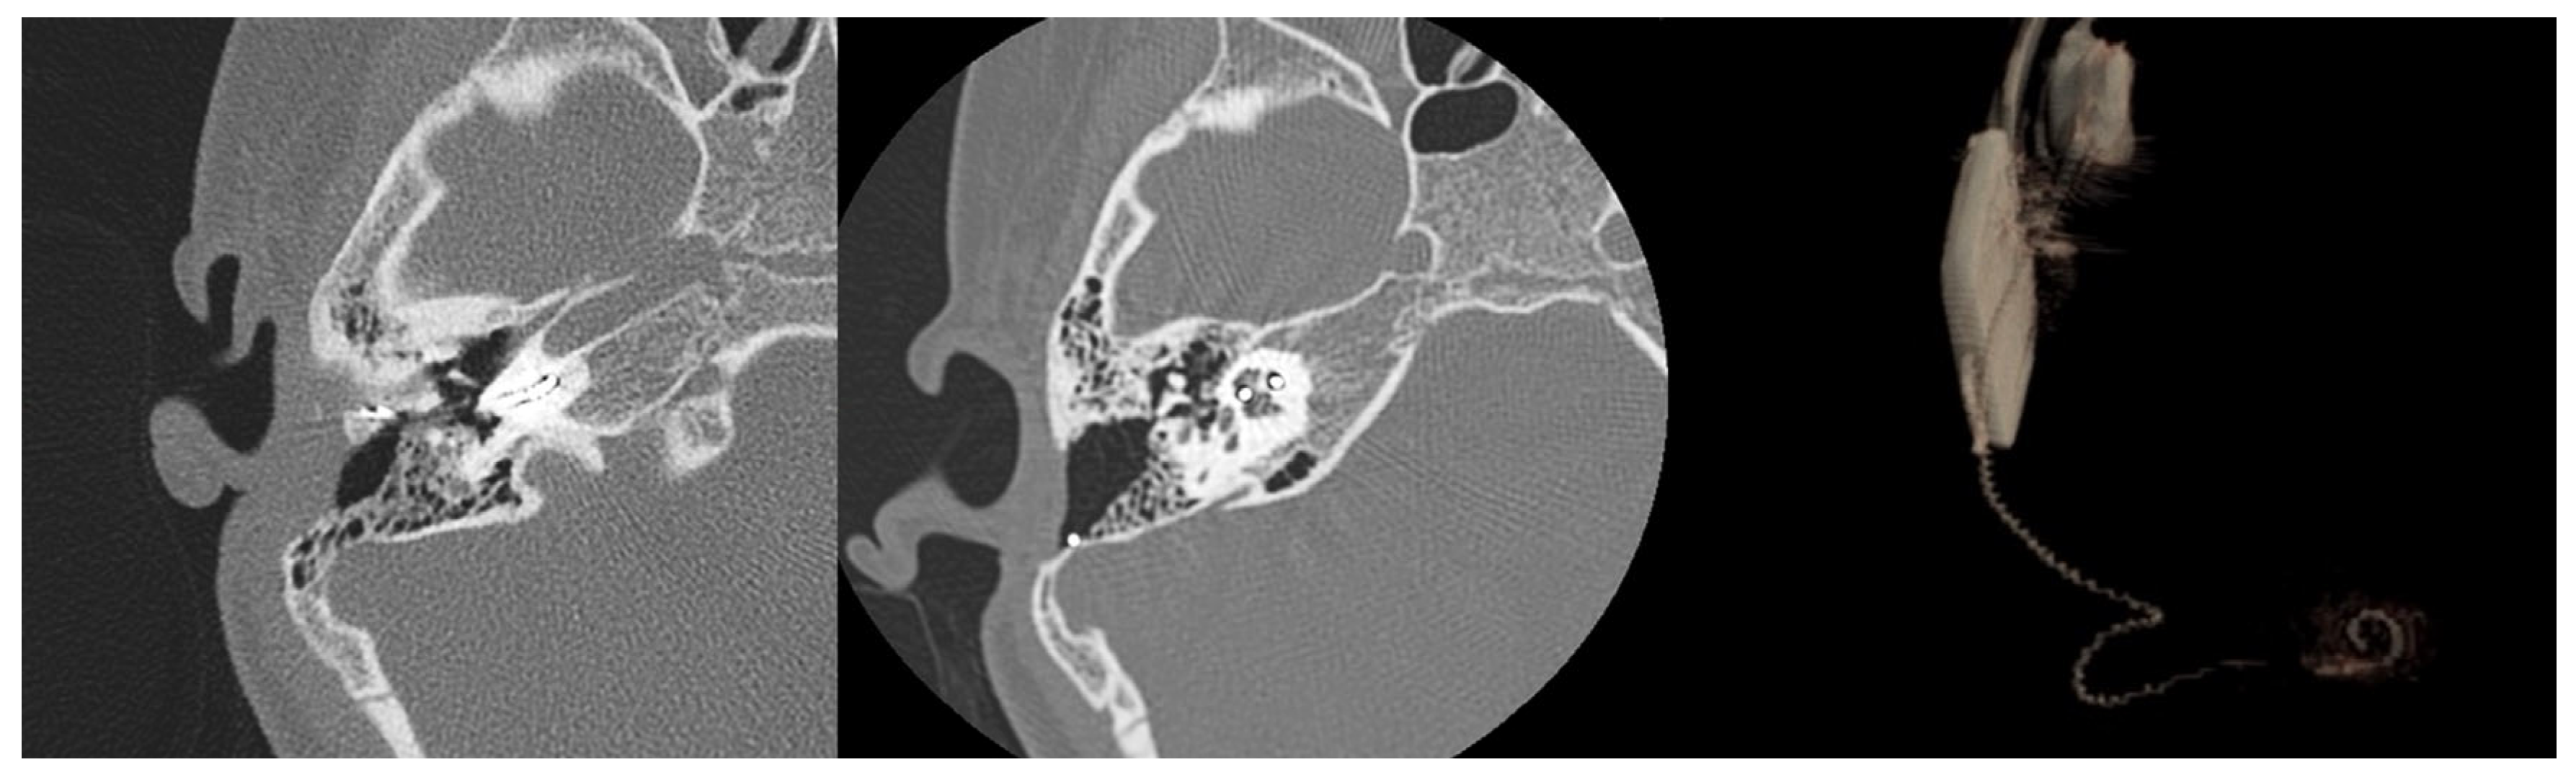

Four months after reimplantation, the previous Nucleus slim straight (CI622) patient underwent computed tomography (CT) imaging and audiologic examinations, which demonstrated the correct placement of the device within the cochlea and a favorable hearing outcome (Figure 3 and Figure 4).

It is challenging to provide an exact assessment of the newly inserted electrode array’s position within the scala tympani. Image analysis and the 3D volume rendering of the CT scan images indicate an intermediate position of the CI632 array in the scala tympani (lateral wall versus perimodiolar). This suggests a certain degree of elasticity or flexibility of the fibrous sheath within the inner ear after explantation, potentially explaining the possible use of various electrode arrays for reimplantation surgery (Figure 5).

Figure 3. CT scan images depicting the positioning of the old electrode array CI622 (left image) and the new one after reimplantation with a slim modiolar CI632 (middle and right images). The reconstruction (via volume rendering) of the electrode within the cochlea facilitates visualization of the proper positioning of the new electrode in the scala tympani.